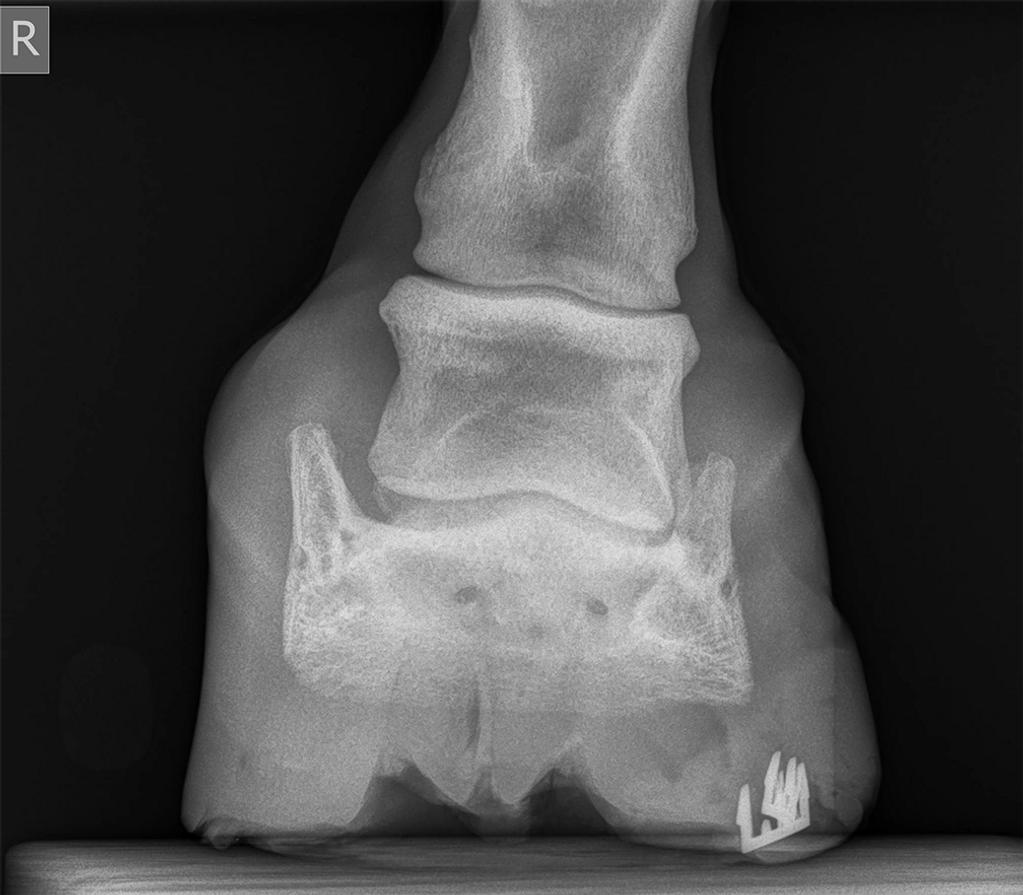

Front View

Horse is 17+ with crooked front legs. It's been a work in progress. He puts all his weight on both inside heels. We started applying two Hoof taps side by side on each inside foot. This progress has been 6 shoeing cycles. Rider says, "he is landing more balanced and feels better than ever!" He even has a better attitude.